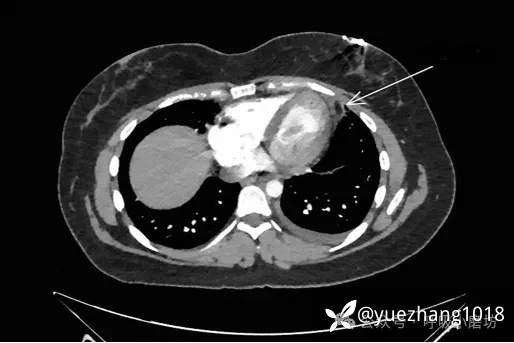

后前位胸部X线片显示有一与左心缘相连的高密度影(图5A),侧位片上位于胸骨后(图5B)。CT显示左心包旁一脂肪病灶伴周围条索影(图5C)。

图5 标注后的后前位及侧位胸部X线片与轴位胸部CT图像